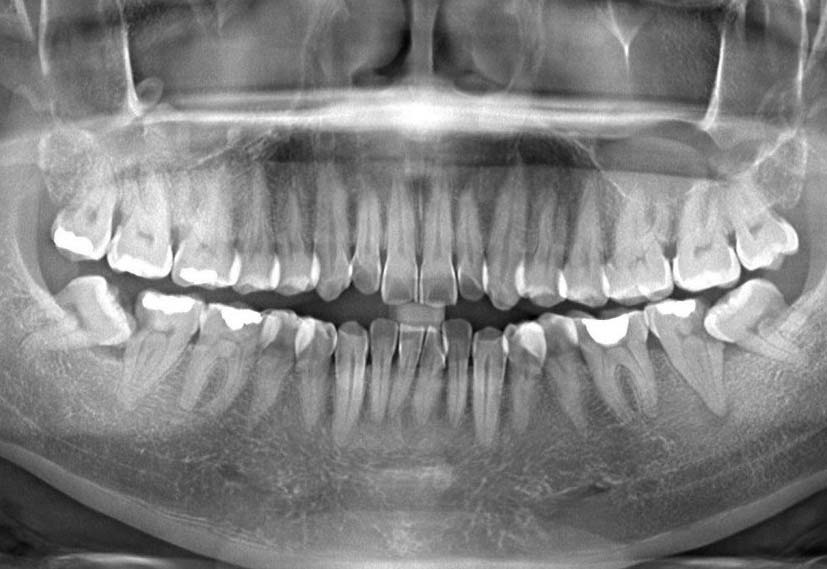

Phòng khám nha khoa Hanseoul được trang bị đầy đủ hệ thống trang thiết bị sử dụng hiện đại: Công nghệ chụp CT, chụp X-quang kỹ thuật số, phần mềm phân tích cấu trúc hàm mặt, công nghệ tẩy trắng hiện đại Laser Whitening, nhổ răng khôn bằng máy siêu âm Piezotome…